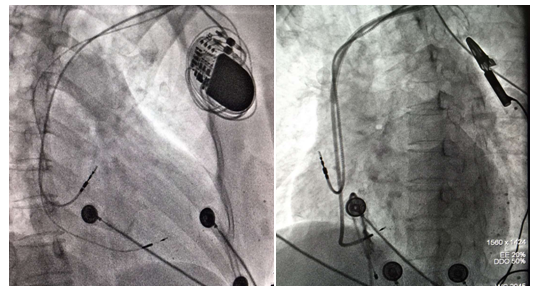

经过与患者及家属积极沟通后,决定为患者行左束支起搏治疗。术前电生理团队制定了缜密的手术方案,于2019年1月22日,在殷跃辉教授的指导下,由我科电生理团队的刘增长教授和杜华安博士成功对患者实施了左束支区域的起搏,纠正了左束支传导阻滞,QRS波明显变窄,约115ms。术后患者心累气促明显好转,日子也开始阳光灿烂起来。患者的远期疗效正在进一步随访评估中。

左束支区域起搏是在希氏束起搏的基础上补充和发展而来的,是一项重大的技术创新,操作更便捷,参数更稳定,急性期和远期阈值更低,不仅解决了希氏束起搏的缺陷,拓宽了适应症,而且费用更低。左束支区域起搏为这位患者提供了最新、最优、最实惠的解决方案,此次手术的成功使我科起搏器治疗领域更上了一个台阶,为更多患者带来了福音。